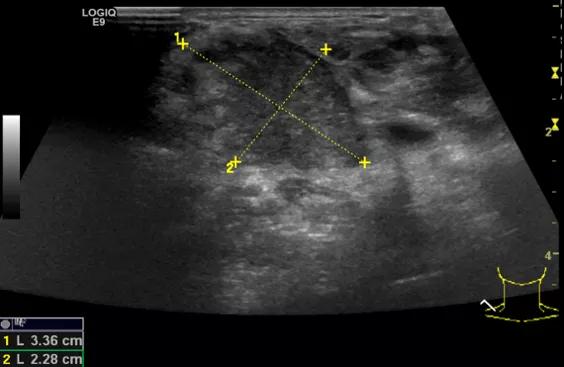

第二例是食管癌患者,术后半年余锁骨上固定淋巴结可触及肿大,疼痛非常明显,系统治疗后无缓解,患者希望通过局部处理缓解症状。造影显示强化信号明显,结节部分区域坏死,故主要针对强化区域从后向前的逐层的消融,皮下进行液体隔离减少烫伤。热消融后影像显示血流增强消失,弹性、硬度增高,一个月后复查显示充盈缺损,完全消融,疗效远超预期。

(病例2图例)